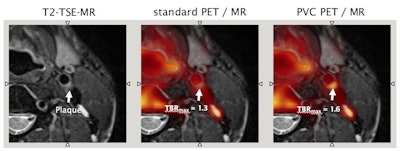

Figure 1: Integrated PET/MRI using [Ga-68]-Pentioxafor (CXCR4) for imaging vulnerable plaque. Correlated MR-based anatomical information can be used for partial volume correction (PVC) of PET tracer uptake in small regions, such as plaques. In this case, T2-weighted turbo spin-echo (TSE) MR image reveals a relatively stable plaque, with regular borders and uniform morphology. The standard PET image does not show increased CXCR4 uptake, while the PVC PET image shows a slight increase of CXCR4 uptake; the tumor-to-background ratio (TBR) increases from 1.3 to 1.6. Images courtesy of Medical University Vienna.

Novel concepts toward intrinsic compensation of involuntary patient motion are being worked on, a prerequisite for subsequent partial volume correction (figure 1), or anatomic-guided image reconstruction. The better the alignment of the two sets of imaging information, the more valuable the clinical information of an integrated PET/MRI examination (figure 2). Also, the palette of PET/MRI scenarios is being expanded through the adoption of the concept of an automated image-derived input function as a prerequisite for parametric imaging, as well as through the adoption of novel radiotracers, such as gallium-68 prostate-specific membrane antigen (Ga-68 PSMA) for multiparametric PET/MR imaging of prostate cancer.